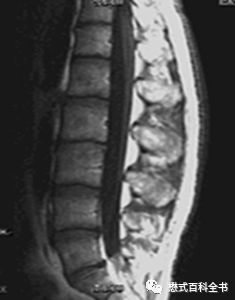

图12~14:非线性梯度的表现

这种图像非常好识别,就是图像变形、扭曲。

出现这种伪影就必须请工程师来检测梯度和调试。